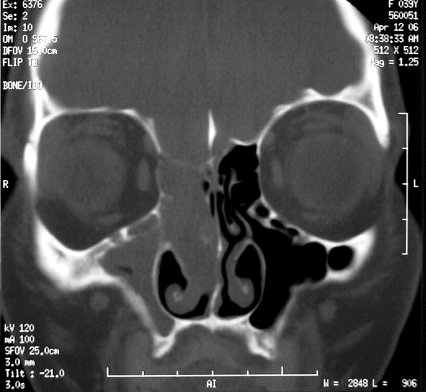

Фронтоэтмоидальное энцефалоцеле.

Цефалоцеле

Приложения:

1._cef.slayd98.jpg